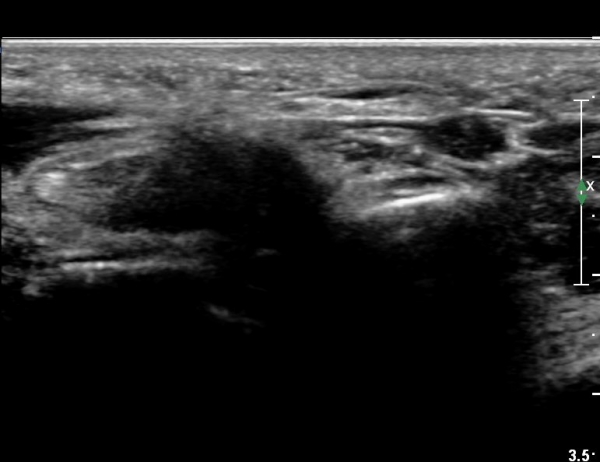

4 sono.jpg